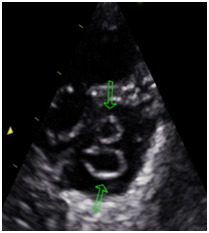

Usually they associated with aortic aneurysm, bicuspid aortic valve, aortic coarctation, subaortic stenosis, patent ductus arteriosus, abnormal interatrial and interventricular septum. They may evolve failure and / or mitral stenosis. (Figures 1–4)

Figure 2 Parasternal short axis. Presence of 4 muscle Papillary. Double mitral orifice.